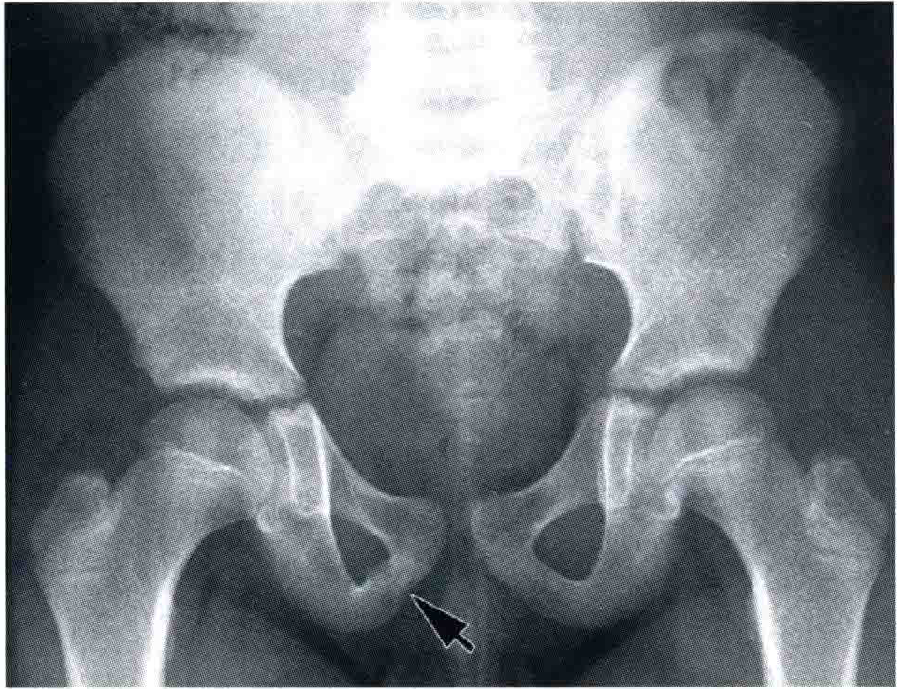

恥骨疲労骨折 恥骨結合炎 古東整形外科 リウマチ科